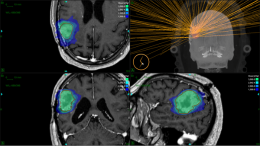

Reirradiation of Large or Multifocal High-Grade Gliomas With Gyroscopic Radiosurgery in Combination With Modulated Electro-Hyperthermia

High-grade gliomas (HGG), grade 3 and 4, according to the 2021 World Health Organization (WHO) CNS5 classification system, are the most prevalent malignancies of the central nervous system (CNS)...read more.